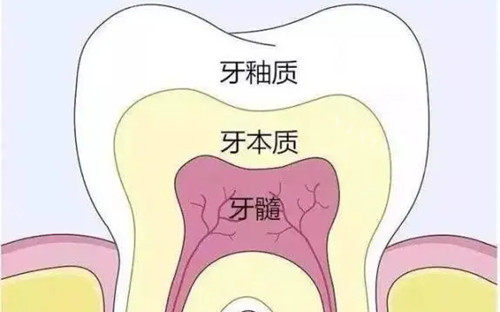

三、牙齿修复价格

牙齿修复包括补牙、烤瓷牙、全瓷牙等项目,帮助患者修养牙齿的外观和功能。

根管治疗:700 元起

前牙根管治疗:320 元起